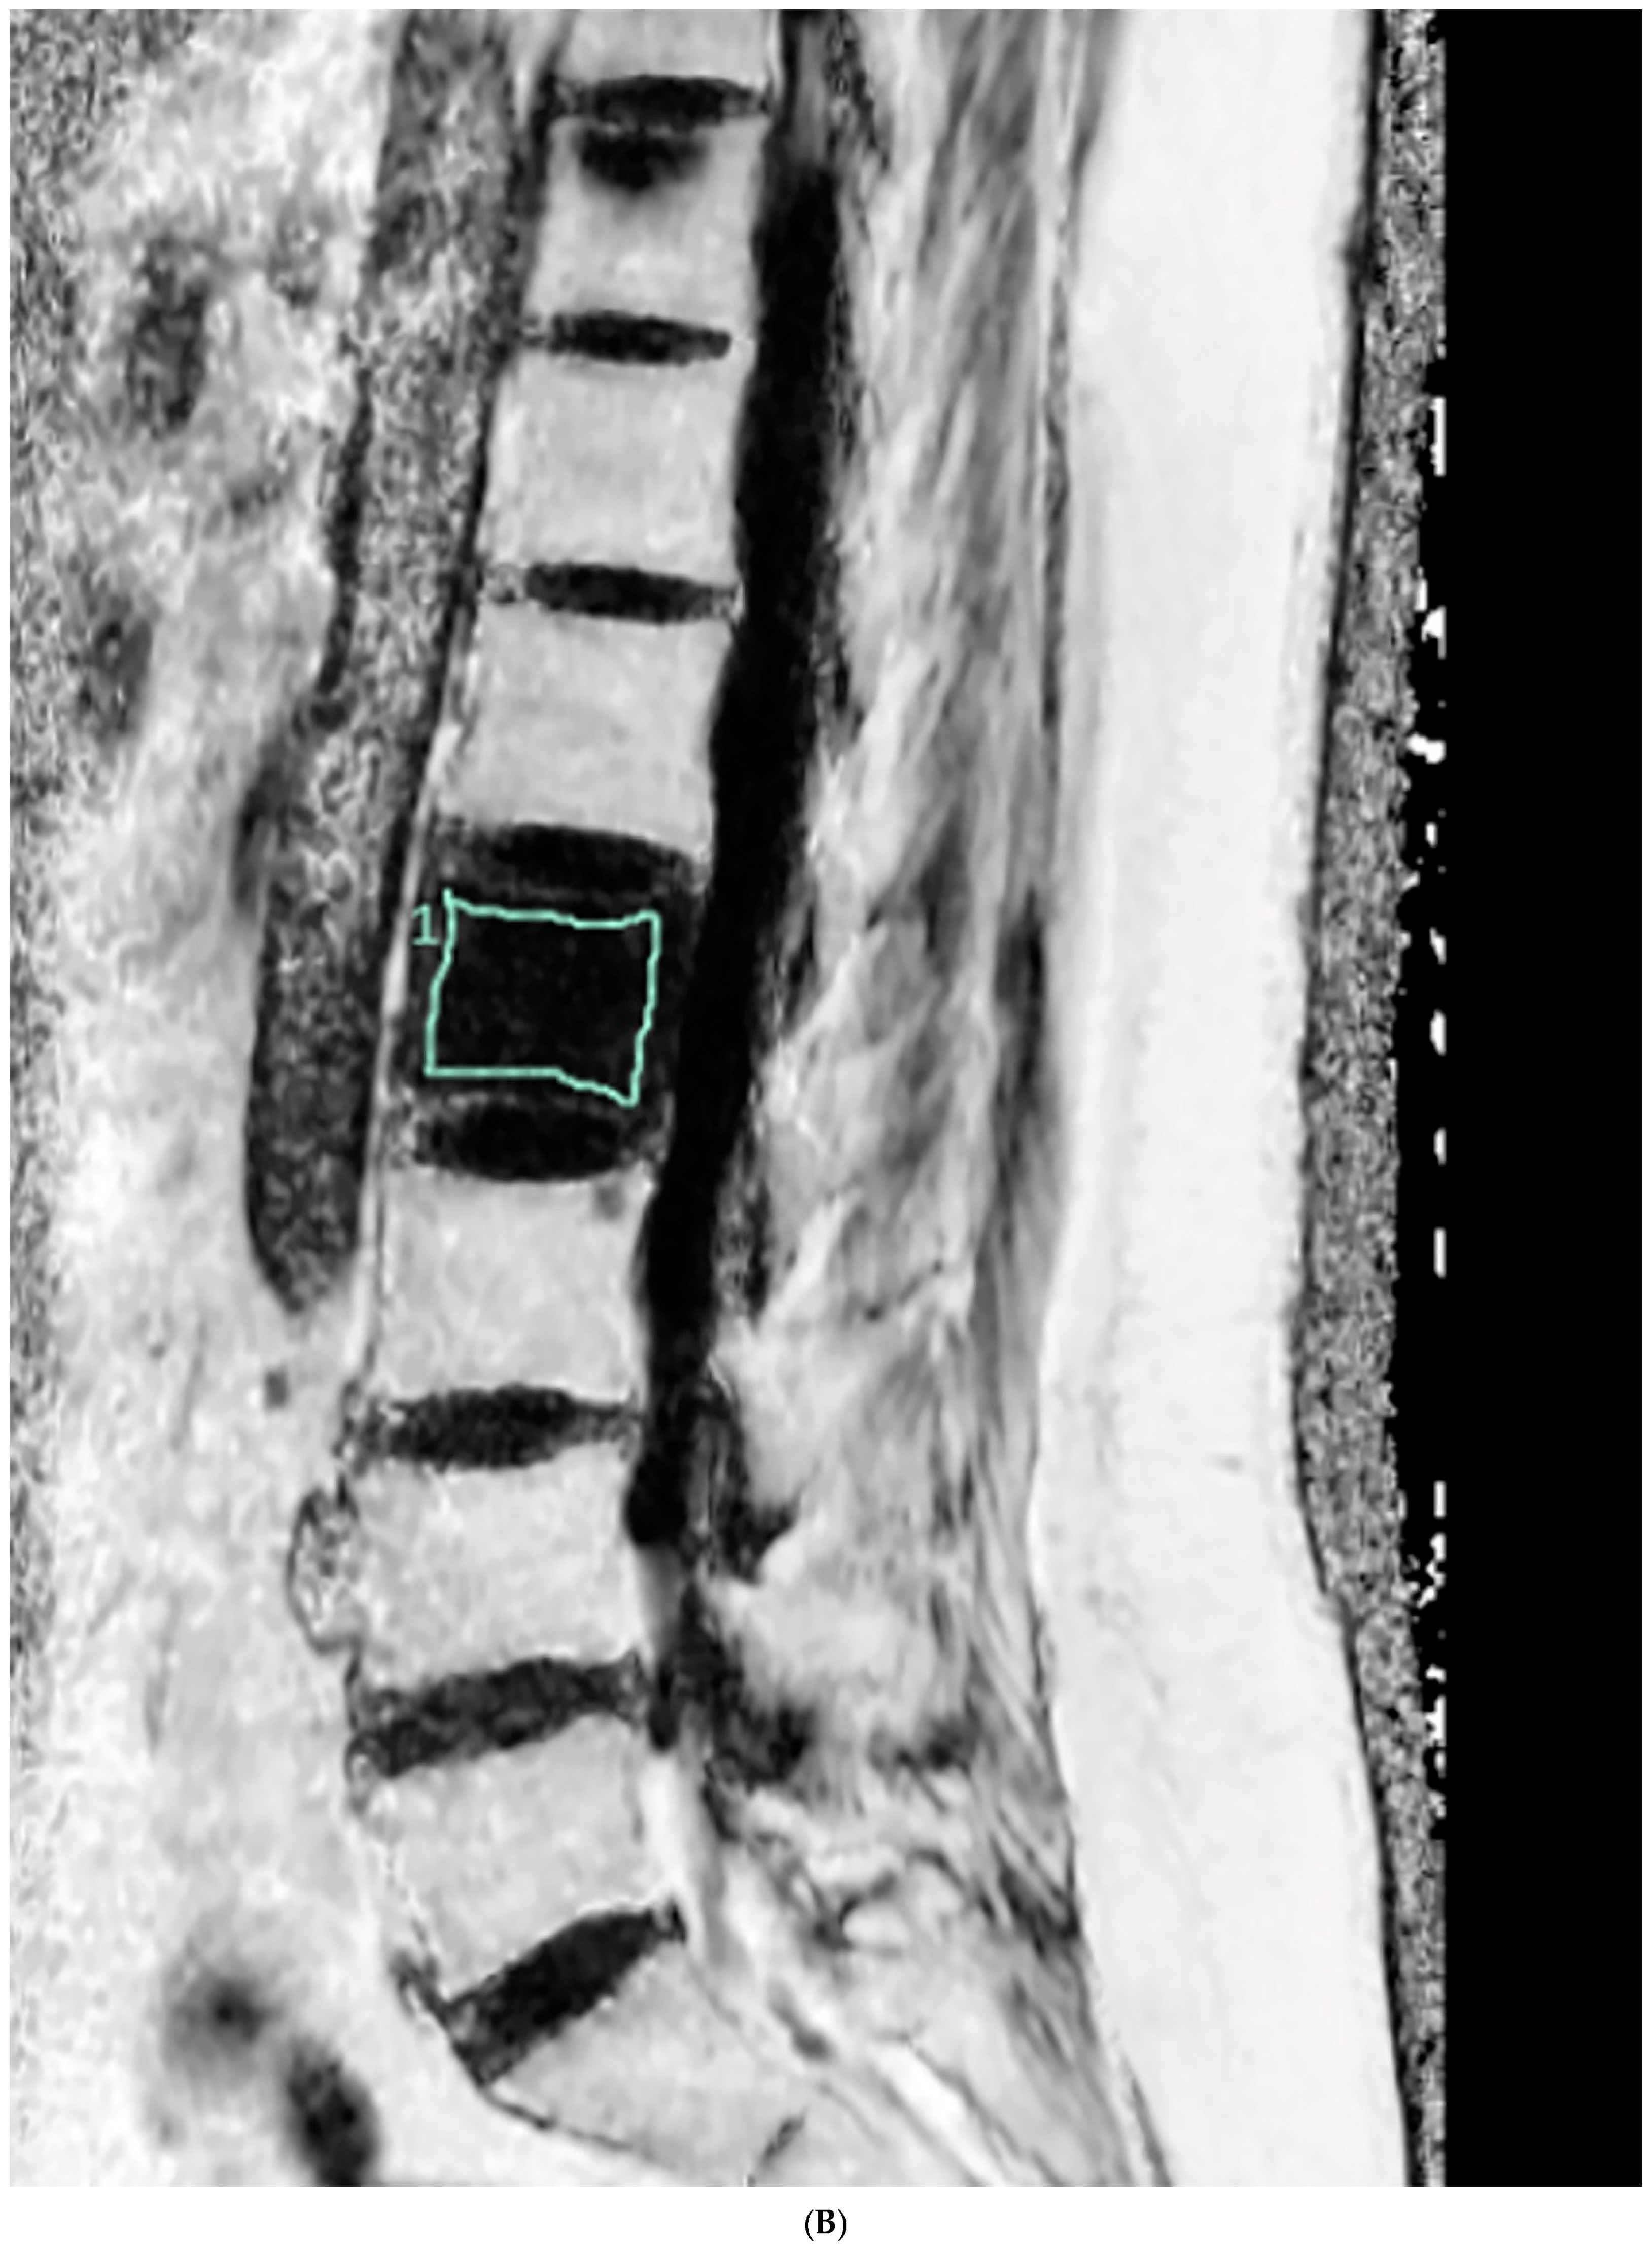

2.4. Vertebral Bone Quality Score Measurement